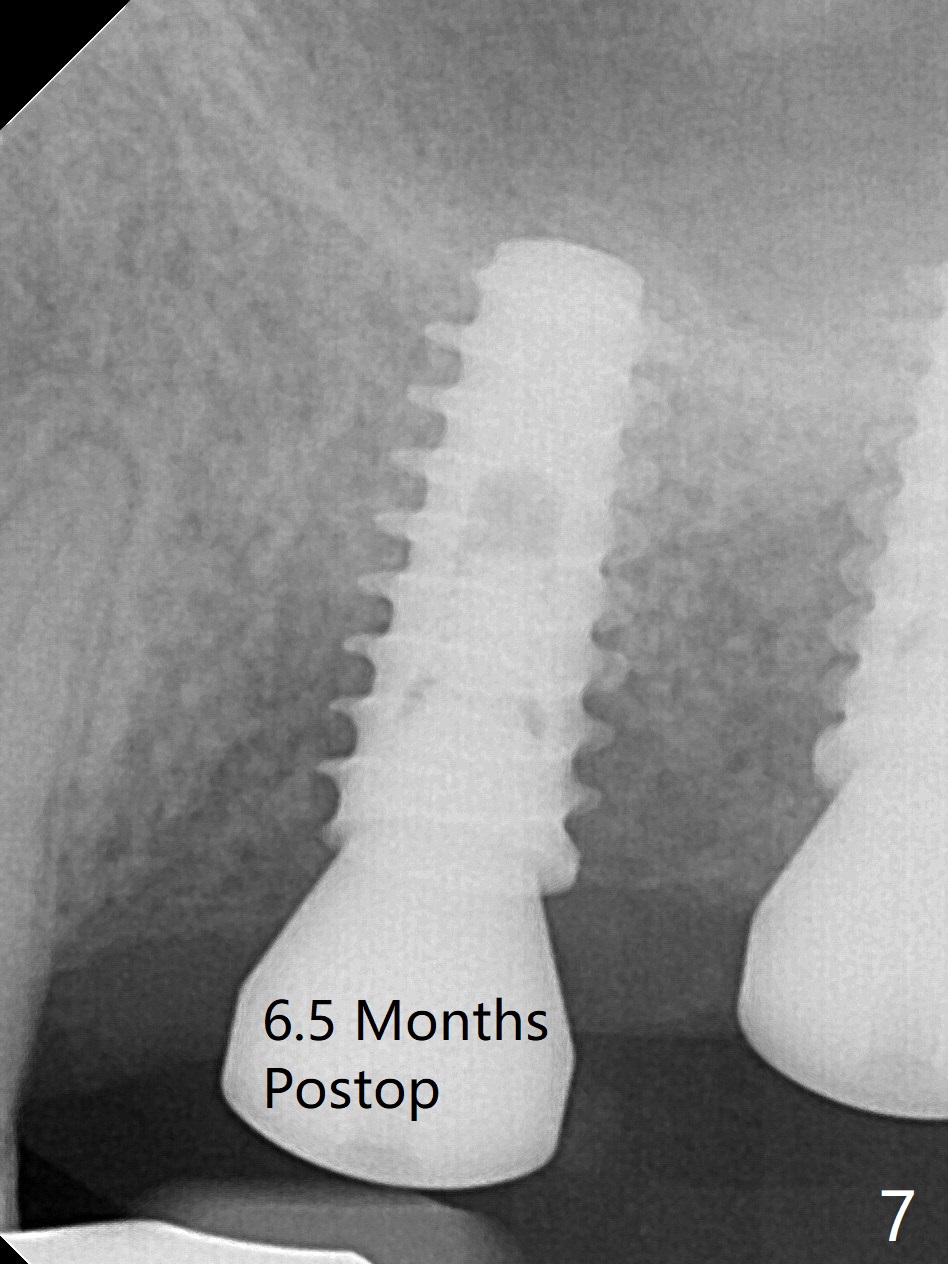

To place 5x11 mm IBS implant (Fig.5), 5.3 mm MD has to be used; prior to implant placement, sinus lift is accomplished with mixture of autogenous bone and Vanilla graft (white *); more allograft (black *) is placed around the implant before insertion of a 6x5.7(3) mm abutment. More allograft is placed around the abutment (Fig.6 *) prior to an immediate provisional fabrication. The grafted bone appears to become the native bone, although at the low density, 6.5 months postop (Fig.7).